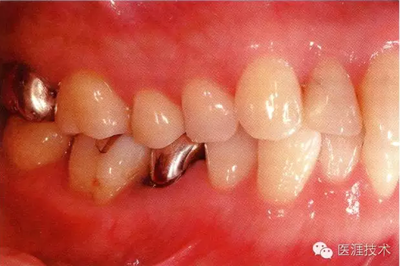

55歲牙周炎男性的臨床照片

55歲男性抽煙患者(1天20支、抽煙35年)。菌斑控制得不好。通過牙周探診,全頜有4~9mm的牙周袋,有1~3度的根分叉部病變。通過X光片觀察,上頜前牙中度牙槽骨吸收,其他地方有中度牙槽骨吸收。受吸煙影響,牙齦纖維性肥厚,呈紅黑色。牙齦幾乎沒有浮腫和發(fā)紅,所以這個病例是從外觀上無法預(yù)測病癥嚴(yán)重程度的病例。